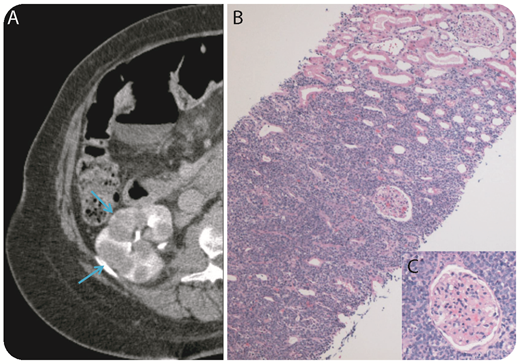

A 69-year-old woman presented to her primary care physician with an enlarging circumferential neck mass and difficulty swallowing. A bronchoscopy with fine needle aspiration was compatible with a CD10+, TdT− B-cell lymphoma with a high proliferation rate (Ki-67 > 95%). Cross-sectional imaging of her chest, abdomen, and pelvis revealed extensive disease with a large mediastinal mass and extranodal disease, including omental caking and multiple bilateral kidney masses (panel A). There was no additional lymphadenopathy in the chest, abdomen, or pelvis. Remarkably, kidney function was normal. Core biopsy of the right kidney revealed sheets of large neoplastic cells with irregular nuclei, vesicular chromatin, and a blastoid morphology, sparing the glomeruli (panel B, original magnification ×10, hematoxylin and eosin stain; panel C, original magnification ×100, hematoxylin and eosin stain). Neoplastic B cells expressed CD20 (weak), CD79a, PAX5, CD10 (weak), and BCL2by immunohistochemical stains. Fluorescence in situ hybridization analysis revealed rearrangements in MYC (59%) and BCL6 (43%) genes and translocation involving IGH-BCL2 (50%) consistent with a “triple-hit” high-grade B-cell lymphoma.

The patient is currently receiving chemotherapy with dose-adjusted rituximab, etoposide, prednisone, vincristine, cyclophosphamide, and doxorubicin. This case shows how “triple-hit” lymphoma can present atypically with limited lymphadenopathy and diffuse extranodal disease and consequently the high risk of secondary central nervous system disease.